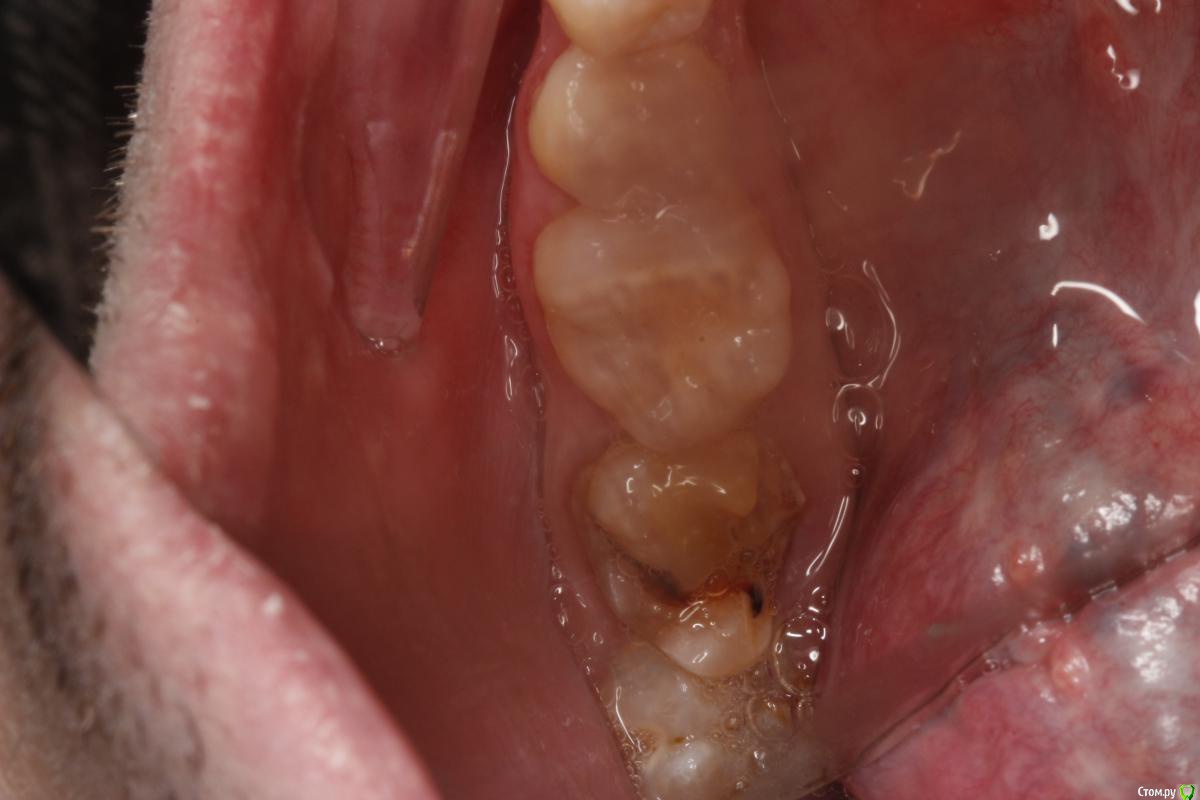

Boris87 Опубликовано 21 марта, 2020 Поделиться Опубликовано 21 марта, 2020 (изменено) Здравствуйте. В 2008 г. нижняя семёрка была депульпирована. Не беспокоит, но откололся небольшой край зуба (года 2 назад уже), и вокруг пломбы уже кариес. Иногда когда ем из того места чувствуется неприятный привкус. Рядом на восьмёрке небольшой кариес, и она упирается в край 7-го. Походил по клиникам. Одни говорят - восьмёрку удалять, на семёрку коронку. Другие - что и семёрку удалять. Ещё в одной сказали что восьмёрку даже можно оставить, пролечив кариес, и обточив семёрку чтобы ей не мешала + коронку, но другие говорили что так никто не обтачивает. В одной клинике говорили что могут просто нарастить светоотвержд. материалом. Я конечно хотел бы этого. Коронку не хочется (читал что металл в организме у многих потом проблемы вызывает, даже рак, особенно если никель в составе). А полностью диоксид циркония дорого, и не уверен что оправданно (зуб потом наверное всё равно удалять). Как тут лучше поступить? ЗЫ. ОПТГ делал в октябре, после этого 5-й зуб был пролечен, а КТ - недавно. Изменено 21 марта, 2020 пользователем Boris87 Ссылка на комментарий

red_butler Опубликовано 21 марта, 2020 Поделиться Опубликовано 21 марта, 2020 Восьмой удалять, седьмой убрать пломбу и кариес и принимать решение, но на фото прогноз седьмого зуба плохой 1 Ссылка на комментарий

DmitrySH Опубликовано 21 марта, 2020 Поделиться Опубликовано 21 марта, 2020 Восьмой удалять, седьмой убрать пломбу и кариес и принимать решение, но на фото прогноз седьмого зуба плохойСогласен. По фото мало понятно. Ссылка на комментарий